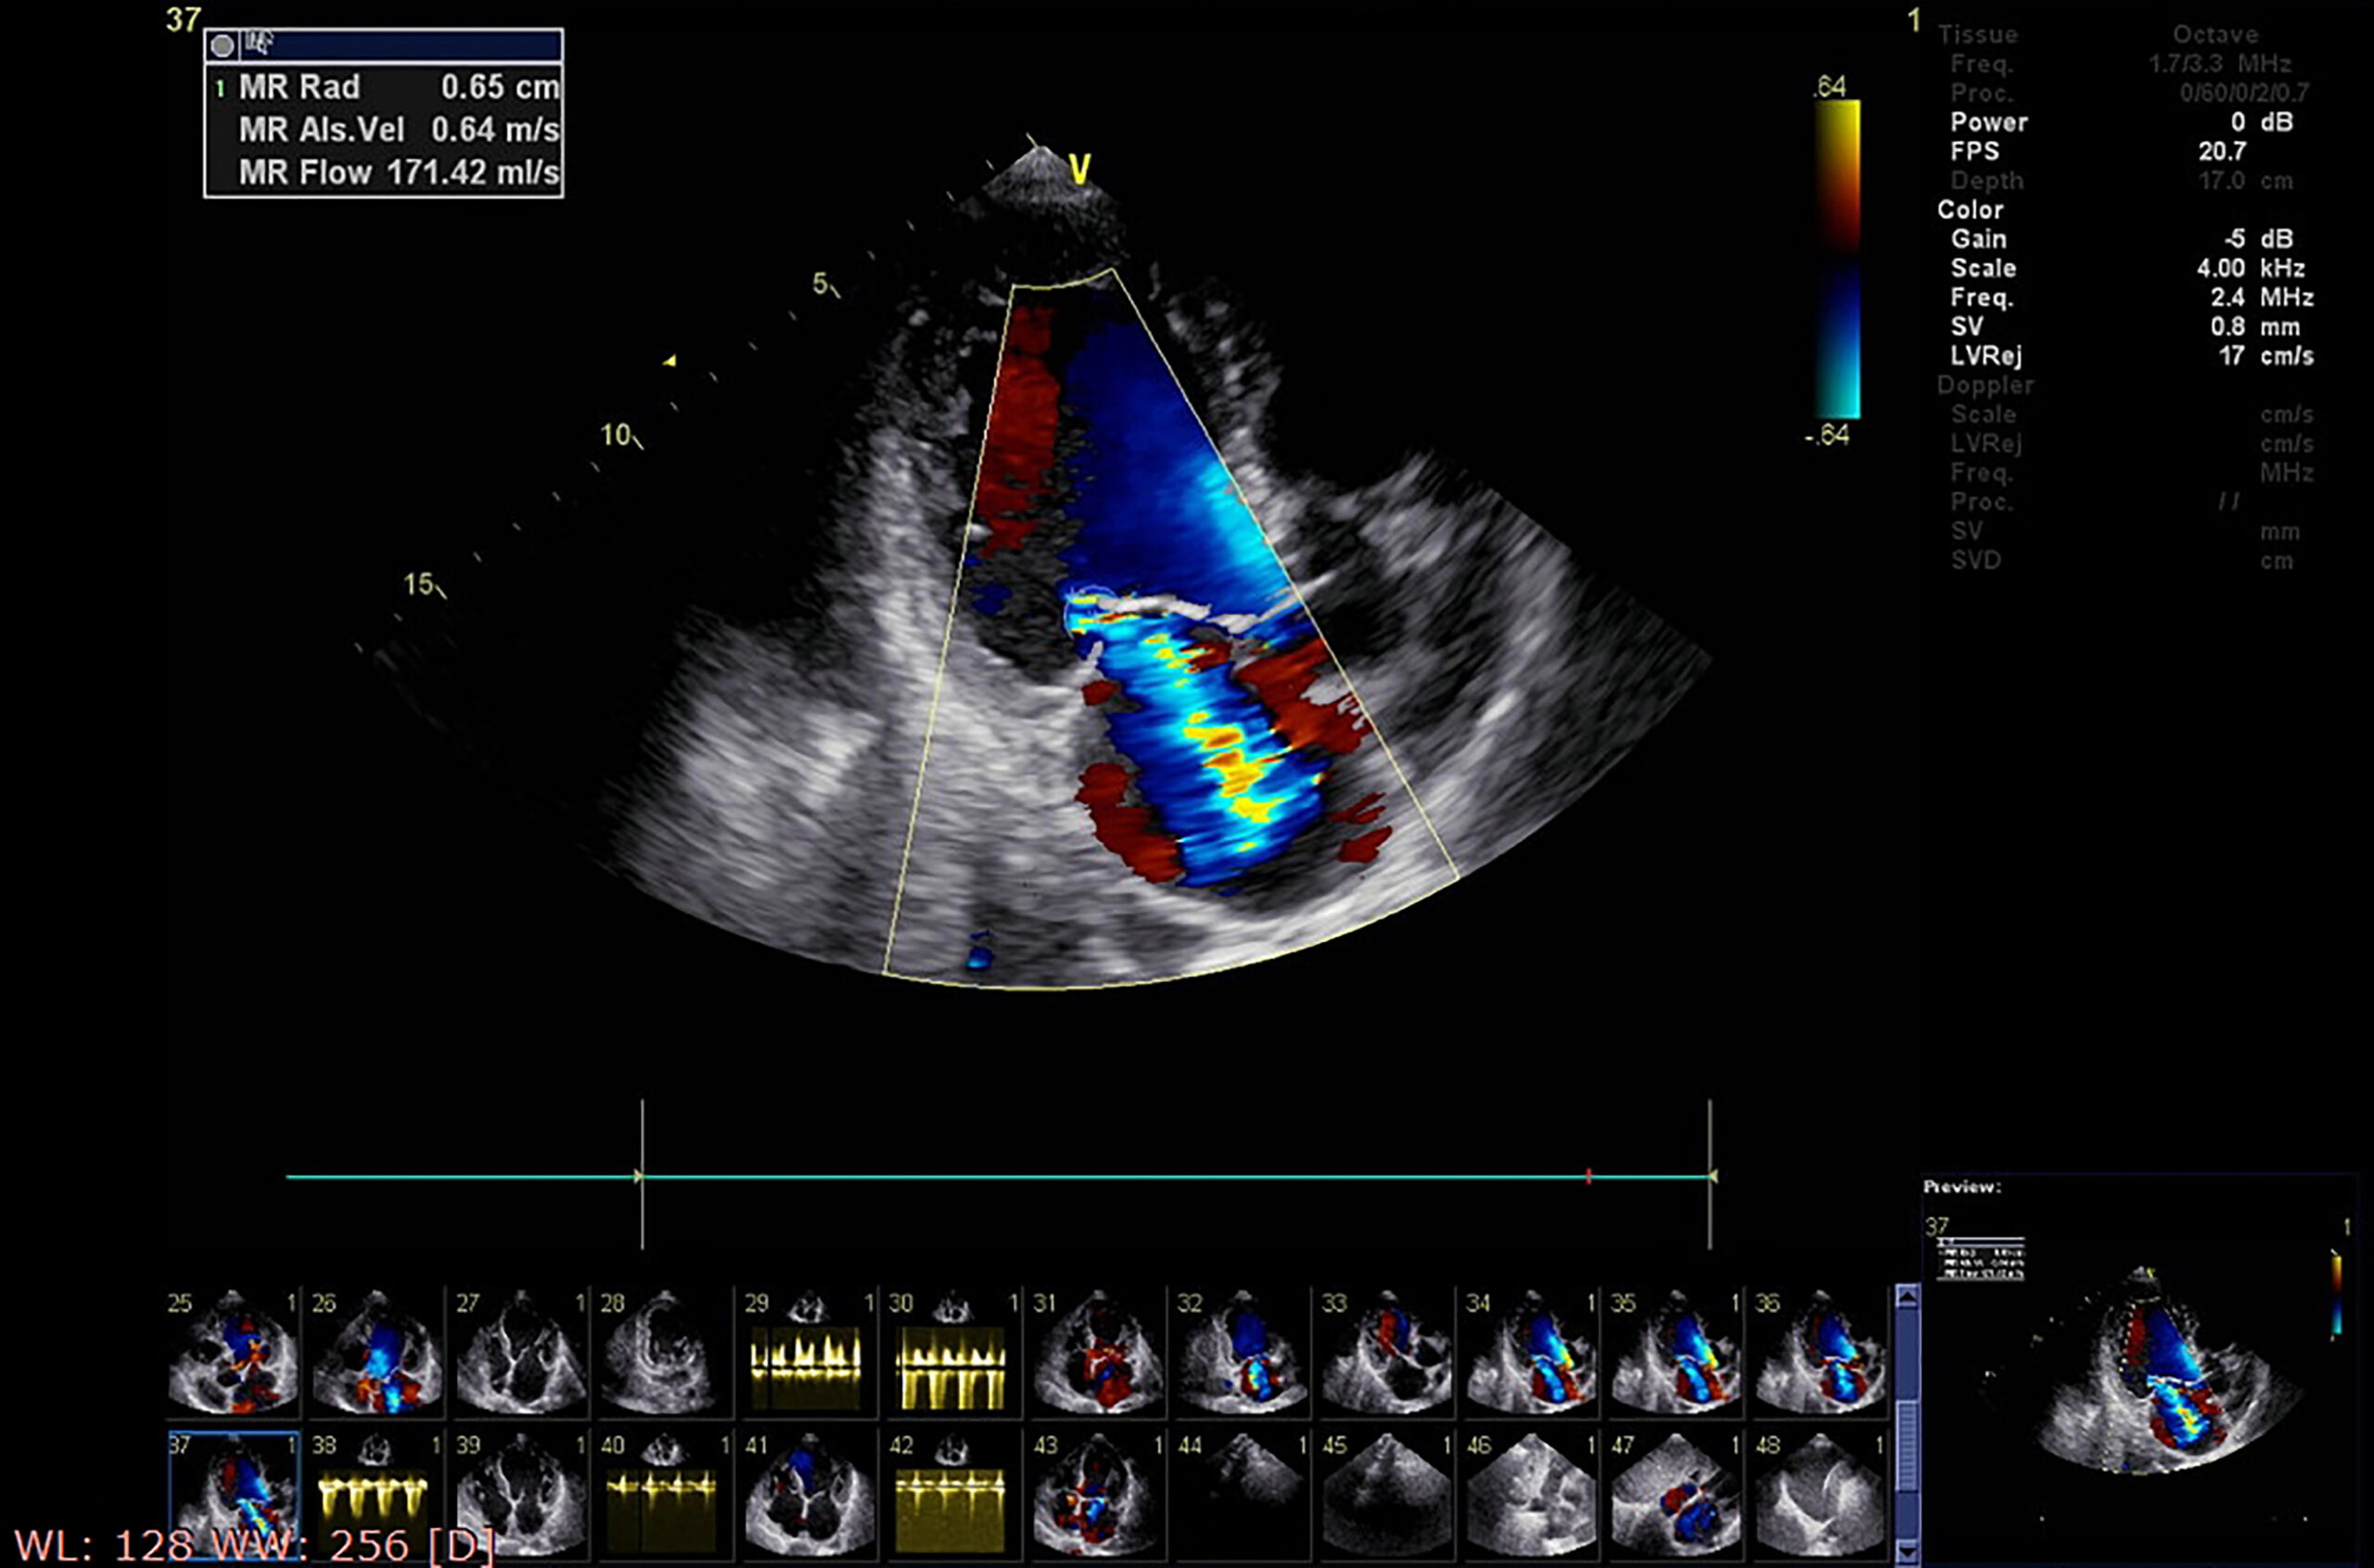

Mit einem hochwertigen Ultraschallgerät wird von der Körperoberfläche aus das Herz zweidimensional von verschiedenen Blickwinkeln aus dargestellt. Dadurch erhält der Arzt Informationen zu der Größe und Funktion des Herzens.

Fehlfunktionen der Herzklappen, Veränderungen durch Bluthochdruck und unterschiedliche Formen von Herzschwäche, angeborene Herzerkrankungen oder eine Herzmuskelentzündung können diagnostiziert werden.